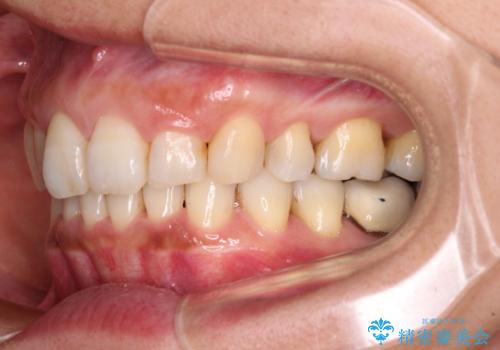

- 以前行った抜歯矯正が後戻りし、開いてしまったスペースが気になるとのことで来院された患者様です。

インビザラインを用いて開いてしまったスペースと前歯のデコボコを改善することとしました。

矯正治療後には気になっていた銀歯をセラミッククラウンやセラミックインレーにて治療することとしました。

上顎前歯を左右対称となるように歯列を整えたいとのことでしたが、すり減って形態が大きく異なっていたため、できる範囲での仕上がりとなりました。